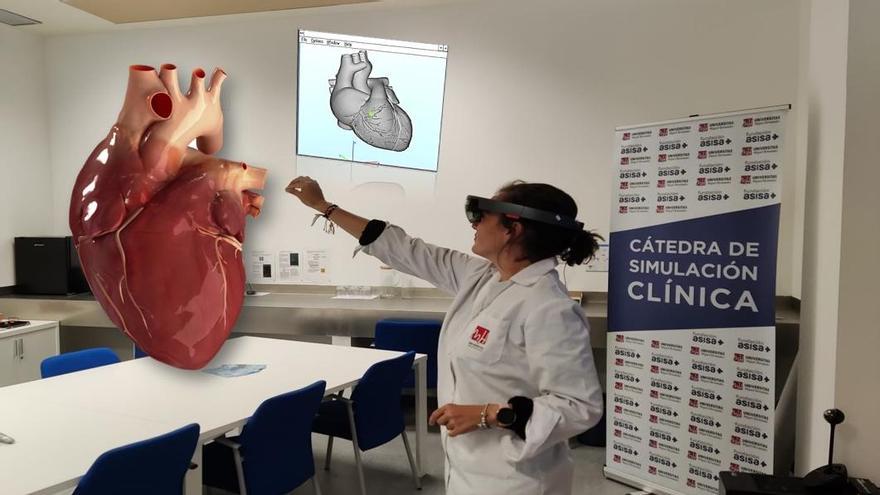

Cátedra de simulación clínica de la Facultad de Medicina / INFORMACIÓN

Este mismo departamento está iniciando un programa piloto de aprendizaje con realidad virtual inmersiva y tridimensional para algunas asignaturas de Medicina, Podología, Fisioterapia y Terapia Ocupacional en el que el estudiante elige el foco, por ejemplo, para hacer un vendaje, estudiar huesos o músculos. "Estamos iniciando el programa para ver si se aprender mejor con menor coste" que otras prácticas en Anatomía.

Sistemas que se utilizan en el proyecto Cyborg de Anatomía